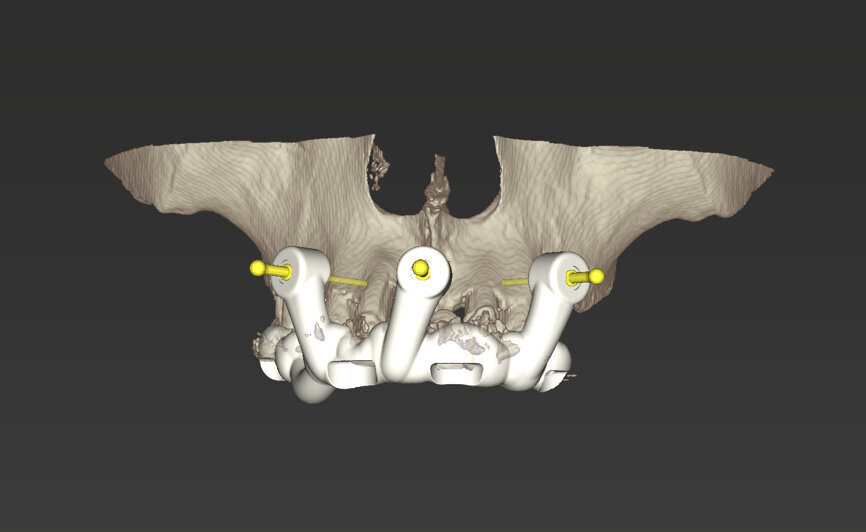

An intra-oral scan was taken to record the patient’s current oral situation, and the resulting STL file and the DSD fil (2D smile design image) were used to create the future prosthetic design with software for the laboratory (Figs. 3–6). The 3D radiographic DICOM data and the prosthetic design project STL file were superimposed in coDiagnostiX (Figs. 7–9) The fixation pin guide, bone reduction guide, surgical guide and bite registration guide were designed with coDiagnostiX (Figs. 10–13) and produced using 3D printing technology.

On the day of surgery, we prepared for the surgical protocol provided by the implant planning software, which guided us on the drilling sequence and the use of the appropriate instruments for the implant bed preparation (Figs. 30a & b). After the fixation pins had been allocated, teeth #17, 16, 15, 13, 12, 22, 23 and 24 were atraumatically extracted and alveolectomy was performed using a bone reduction guide (Figs. 31–36). Four implants (Straumann BLX; regular base; diameter: 4.5 mm; length: 12.0 mm) were placed, two straight implants in the anterior and two titled implants in the posterior. All the implants were stabilised to a torque of 50 Ncm (Figs. 37–43), and the SRAs were placed on top. The SRAs on the posterior implants had an angulation of 30° (diameter: 4.6 mm; gingival height: 3.5 mm) and on the anterior implants an angulation of 17° (diameter: 4.6 mm; gingival height: 3.5 mm; Figs. 44 & 45).